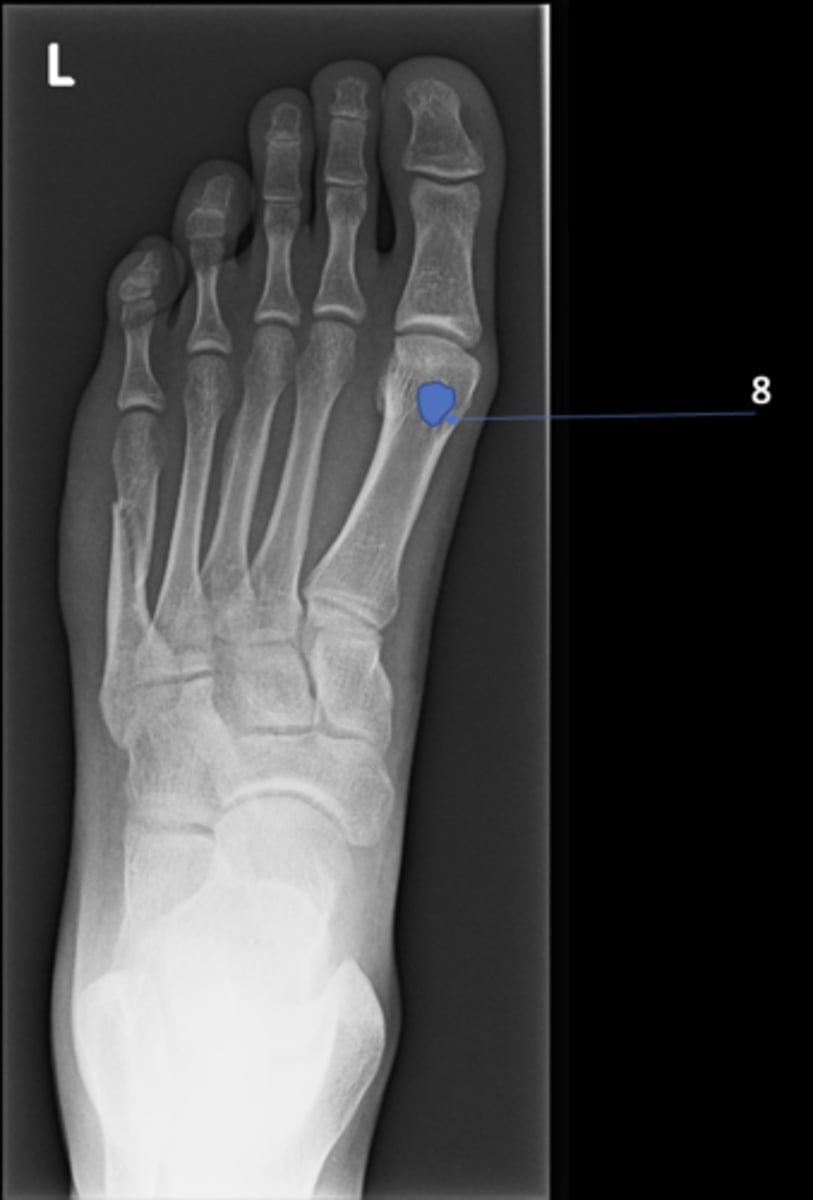

8

Left ischial spine

ID 8

<p>ID 8</p>